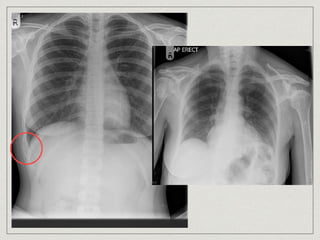

Ewing’s sarcoma

small round cell sarcoma

15% presented at chest wall, 17% all primary chest wall tumor

age >40 years old, male x2> female

painfull, enlarging mass associated with fever, malaise,

leukocytosis, anemia, increase ESR

mottled destruction containing lytic and blastic area, onion skin

appearance

medical treatment, surgical role to biopsy

5-year survival 48%

Ewing’s sarcoma small roundcell sarcoma 15% presented at chest wall, 17% all primary chest wall tumor age >40 years old, male x2> female painfull, enlarging mass associated with fever, malaise, leukocytosis, anemia, increase ESR mottled destruction containing lytic and blastic area, onion skin appearance medical treatment, surgical role to biopsy 5-year survival 48%